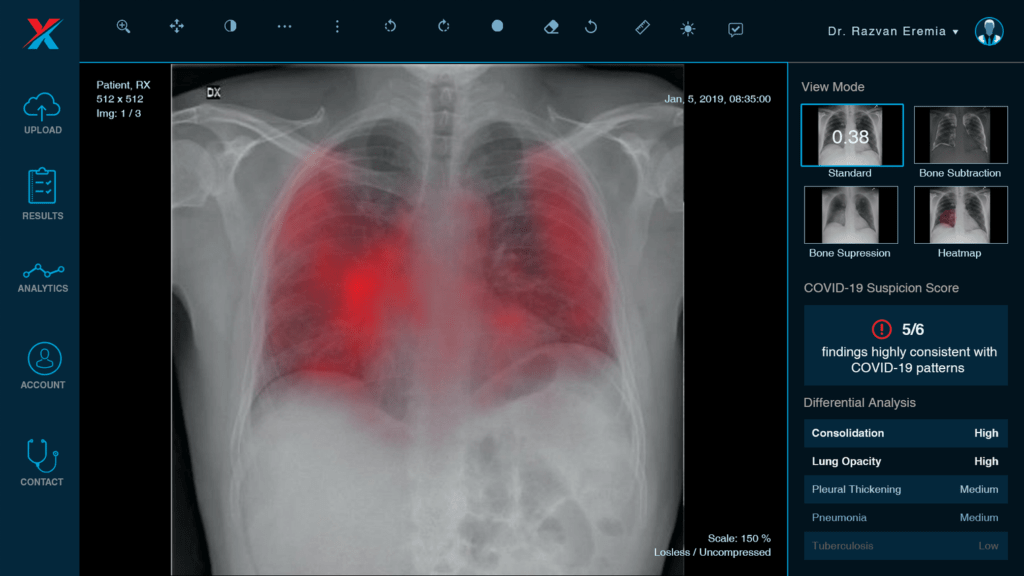

Softul dezvoltat de start-up-ul XVision, format dintr-o echipă tânără de IT-iștiși medici radiologi,extrem de activi și documentați, îmbină perfect medicina modernă cu tehnologia. Sistemul folosește inteligența artificială pentru a genera interpretări ale radiografiilor pulmonare, fiind menit să asiste doctorii în analiza pe care o fac, oferind în mod rapid o interpretare adițională a imaginilor medicale, asemenea unui ‘coleg’ digital. Folosirea aplicației facilitează procesul de screening și prioritizează pacienții în funcție de patologiile detectate, putând fi folosit și pentru screening-ul pentru COVID-19.